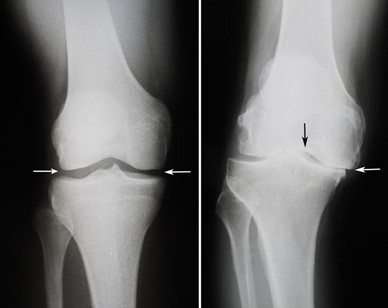

• Radiografías. Estas imágenes ayudan a determinar el grado de daño y de deformidad de la rodilla.

(Izquierda) En esta radiografía de una rodilla sana, el espacio entre los huesos indica que el cartílago está sano (flechas). (Derecha) Esta radiografía de una rodilla que se ha arqueado por la artritis muestra que hay una pérdida importante del espacio articular (flechas).